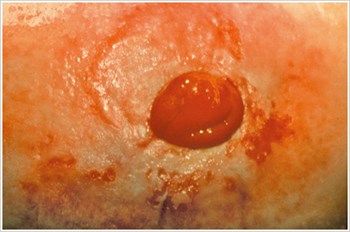

Pyoderma Gangrenosum

Popis/příčiny:

Zánětlivé kožní onemocnění, které se často vyskytuje u pacientů se zánětlivým onemocněním střev (IBD), jako je Crohnova choroba nebo ulcerózní kolitida.

Symptomy:

- Nepravidelně tvarované, červené, bolestivé, infikované vředy, s červenými až fialovými svinutými okraji; se objevují na nohou, hýždích, obličeji a peristomální oblasti.